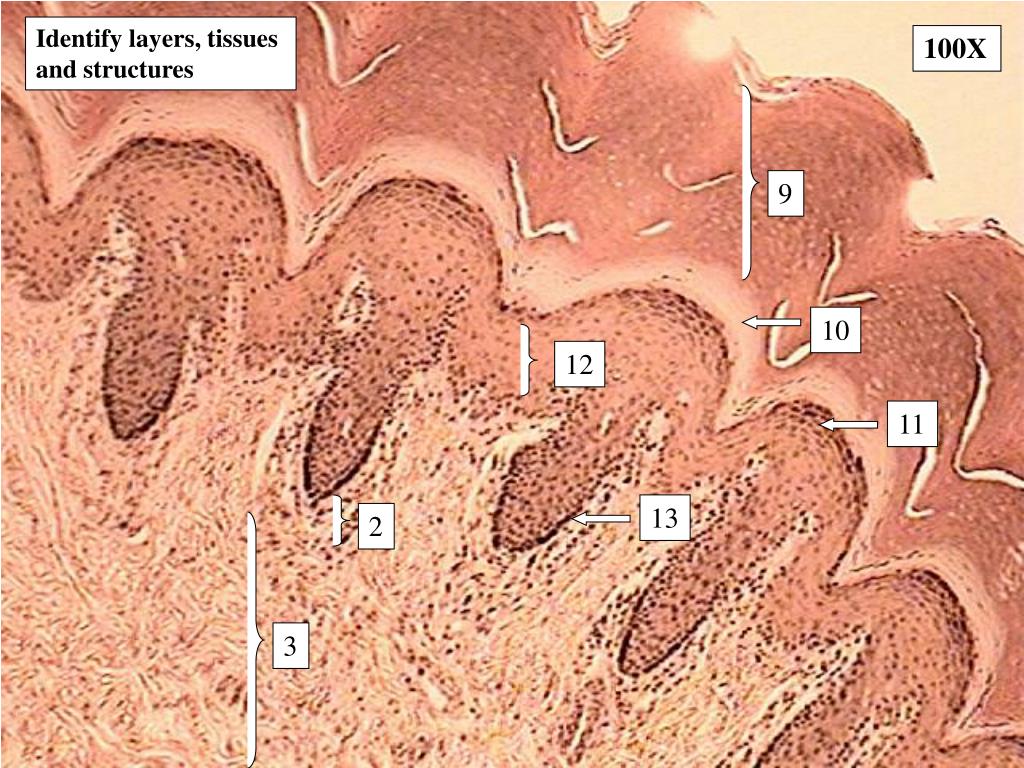

5. Identify layers, tissues and structures 100X 9 10 12 11 13 2 3

13. Answers to Integumentary Slides Slide 3: Human scalp overview Slide 4: Human scalp low power Slide 5: Primate finger tip low power epidermis/dermis interface Slide 6: Human scalp high power epidermis/dermis interface Slide 7: Primate fingertip high power of epidermis Slide 8: Human scalp high power of dermis Slide 9: Human scalp high power dermis/hypodermis interface Slide 10: Primate finger tip high power of the dermis Slide 11: Primate finger tip high power of the dermis Slide 12: Pancreas high power

14. Answers to Integumentary Slides Guide to numbers: • Layer: Epidermis Tissue: Keratinized Stratified Squamous • Layer: Papillary region of the dermis Tissue: Areolar tissue • Layer: Reticular region of the dermis Tissue: Dense Irregular Connective Tissue • Layer: Hypodermis Tissue: Adipose tissue • Hair shaft • Arrector Pili muscle • Sebaceous gland • Sudoriferous (ecrine) gland

15. Answers to Integumentary Slides Guide to numbers: • Stratum Corneum • Stratum Lucidum • Stratum Granulosum • Stratum Spinosum • Stratum Basale or Germinativum • Meissner’s Corpuscle • Dermal Papilla • Pacinian Corpuscle